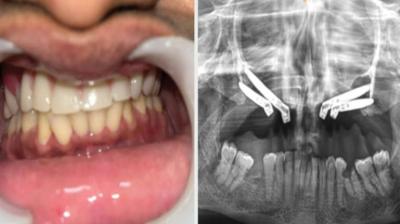

24 वर्षीय युवती के चेहरे पर लौटी मुस्कान और आत्मविश्वास

6 Sep, 2025 10:00 PM IST | SAMNALIVE.COM

एम्म में जटिल सर्जरी को सफलतापूर्वक अंजाम दिया है। इस सर्जरी में ट्यूमर के कारण काटे गए निचले जबड़े को पैर की हड्डी से दोबारा बनाया गया और उसमें 13...